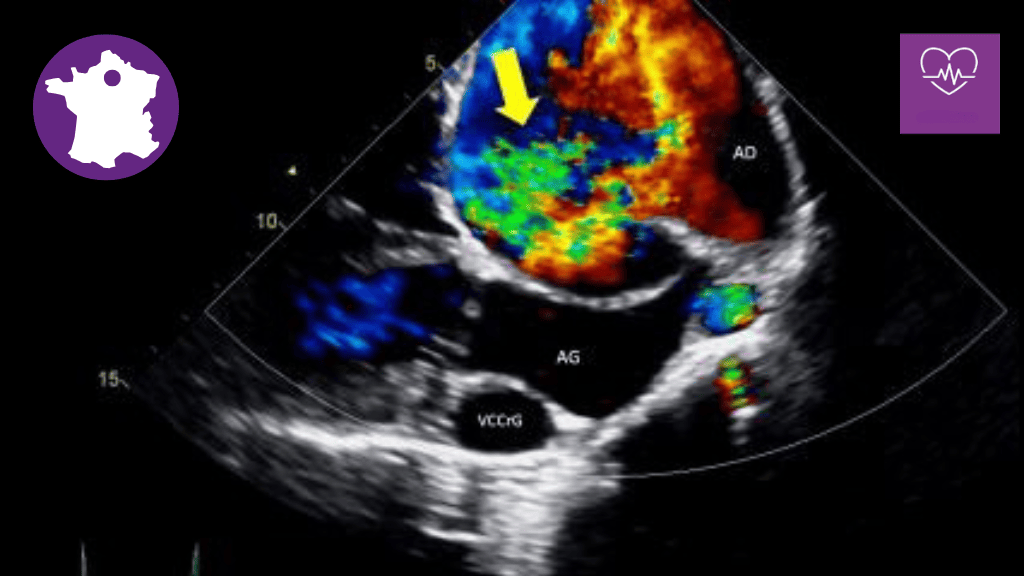

Bannière visuelle de présentation de la formation